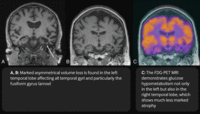

Neuroimaging patterns associated with behavioural variant FTD (bvFTD) and nonfluent variant primary progressive aphasia (nfvPPA). Structural MRI and FDG-PET demonstrating the variability in patterns of atrophy and hypometabolism in FTD. In the case of bvFTD, significant bilateral frontal lobe atrophy and hypometabolism is seen. In the case of nfvPPA, atrophy and hypometabolism is lateralised and is greatly impacting the left frontal lobe more so than the right.

Peet BT et al. Neurotherapeutics 2021 Apr; 18 (2): 728-52; used with permission